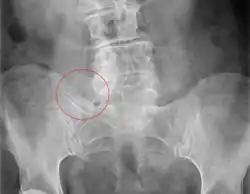

| X-ray of Bertolotti's syndrome (in this case, right transverse mega-apophysis of L5 with pseudoarticulation with the sacral ala). Woman 67 years old. |

Bertolotti's syndrome is a commonly missed cause of back pain which occurs due to lumbosacral transitional vertebrae (LSTV). It is a congenital condition but is not usually symptomatic until one's later twenties or early thirties.[1] However, there are a few cases of Bertolotti's that become symptomatic at a much earlier age.